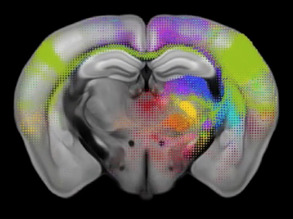

BRCA1 Shapes Brains